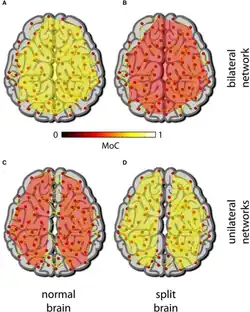

The two hemispheres of the cerebral cortex are linked by the corpus callosum, through which they communicate and coordinate actions and decisions. Communication and coordination between the two hemispheres is essential because each hemisphere has some separate functions.[9] The right hemisphere of the cortex excels at nonverbal and spatial tasks, whereas the left hemisphere is more dominant in verbal tasks, such as speaking and writing. The right hemisphere controls the primary sensory functions of the left side of the body. In a cognitive sense the right hemisphere is responsible for recognizing objects and timing, and in an emotional sense it is responsible for empathy, humor and depression. On the other hand, the left hemisphere controls the primary sensory functions of the right side of the body and is responsible for scientific and math skills, and logic.[10] The extent of specialized brain function by an area remains under investigation. It is claimed that the difference between the two hemispheres is that the left hemisphere is "analytic" or "logical" while the right hemisphere is "holistic" or "intuitive".[11] Many simple tasks, especially comprehension of inputs, require functions that are specific to both the right and left hemispheres and together form a one-direction systematized way of creating an output through the communication and coordination that occurs between hemispheres.[12]

The corpus callosum is a structure in the brain along the longitudinal fissure that facilitates much of the communication between the two hemispheres. This structure is composed of white matter: millions of axons that have their dendrites and terminal boutons projecting in both the right and left hemisphere. However, there is evidence that the corpus callosum may also have some inhibitory functions.[13] Post-mortem research on human and monkey brains shows that the corpus callosum is functionally organized.[14] This organization results in modality-specific regions of the corpus callosum that are responsible for the transfer of different types of information. Research has revealed that the anterior midbody transfers motor information, the posterior midbody transfers somatosensory information, the isthmus transfers auditory information, and the splenium transfers visual information.[15] Although much of the inter-hemispheric transfer occurs at the corpus callosum, there are trace amounts of transfer via commissural pathways, such as the anterior commissure, posterior commissure, habenular commissure, and the hippocampal commissure.[16]

Studies of the effects on the visual pathway on split-brained patients has revealed that there is a redundancy gain (the ability of target detection to benefit from multiple copies of the target) in simple reaction time. In a simple response to visual stimuli, split-brained patients experience a faster reaction time to bilateral stimuli than predicted by model.[17] A model proposed by Iacoboni et al.[18] suggests split-brained patients experience asynchronous activity that causes a stronger signal, and thus a decreased reaction time. Iacoboni also suggests there exists dual attention in split-brained patients, which implies that each cerebral hemisphere has its own attentional system.[19] An alternative approach taken by Reuter-Lorenz et al.[20] suggests that enhanced redundancy gain in the split brain is primarily due to a slowing of responses to unilateral stimuli, rather than a speeding of responses to bilateral ones.

The simple reaction time in split-brained patients, even with enhanced redundancy gain, is slower than the reaction time of normal adults.